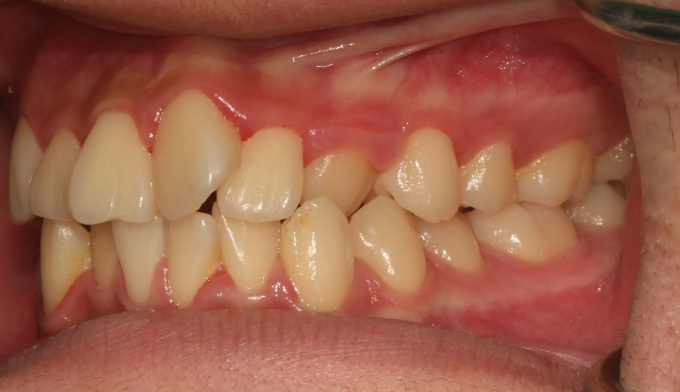

불규칙앞니

불규칙한 앞니를 교정하기 위해선 공간을 만들어야 합니다.

악궁이 좁은 경우에는 확장치료를, 그렇지 않으면 전체 치아를 후방이동시키거나 치아를 삭제하기도 합니다.

이번에는 악궁이 좁은 경우에 해당됩니다. 그 정도가 심해, 윗니 일부가 아랫니보다 안쪽으로 들어가있습니다.

상악확장장치를 통해 악궁을 넓혀주고 치아를 배열해줍니다.

치료기간은 15개월 소요되었습니다.